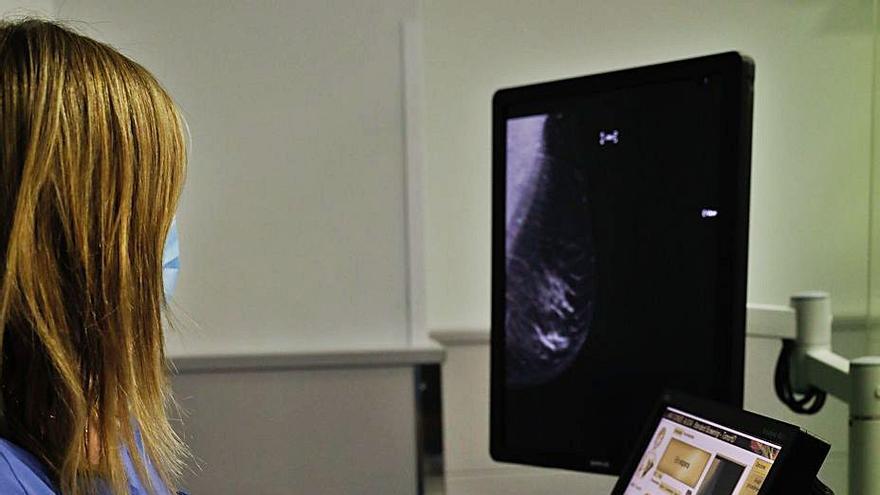

Algo más de 300 personas aguarda, a su vez, por una colonoscopia y 81 por una mamografía, once con cita. La mayoría de estas pruebas que afectan a mujeres con probabilidad de padecer un cáncer de mama se realizan, no obstante, en el Hospital de Avilés.

Diagnóstico de mama

El complejo sanitario de la calle Cabruñana es desde hace 21 años el centro de referencia en el área para la realización de los “screening” de mama, como se conoce en el argot sanitario las pruebas diagnóstico precoz a las mujeres de más de 50 años y que en Avilés suman unas 8.000 al año.

El año pasado el centro estrenó un mamógrafo digital de última generación con múltiples ventajas respecto al anterior equipo: la principal es que no sólo es más sensible para hallar tumores sino que, además, detecta los más pequeños y en estadios más tempranos, lo que incrementa hasta en un noventa por ciento las posibilidades de curación.

Actualmente los especialistas del complejo sanitario de Cabruñana diagnostican un cáncer de mama a la semana, según los últimos datos.